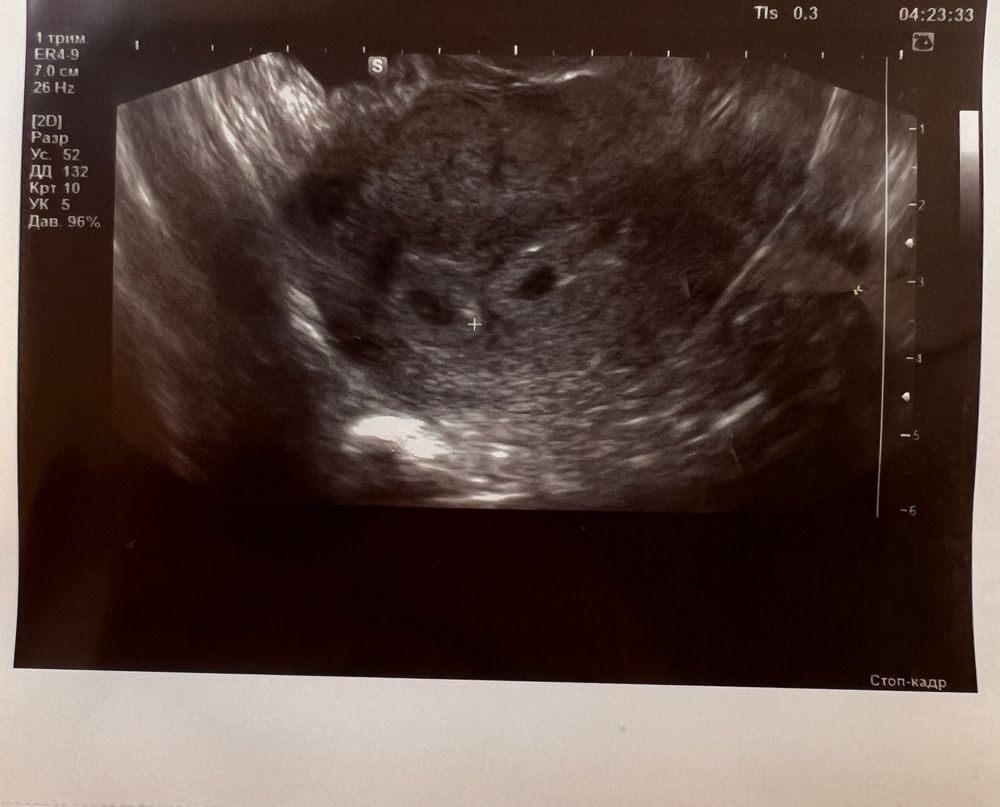

Узи на 23 дпп Быть или не быть Крио Ец 4дц ДФ 15.5